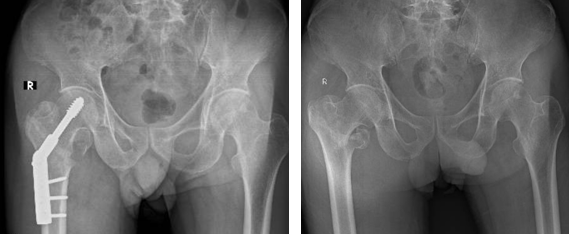

• Phương pháp kết hợp xương bằng nẹp vít: Phương pháp này được chỉ định cho trường hợp gãy xương đơn giản. Các loại nẹp được sử dụng phổ biến gồm: nẹp khóa đầu trên xương đùi, nẹp gấp góc DHS …​​​​​​​

Nẹp DHS